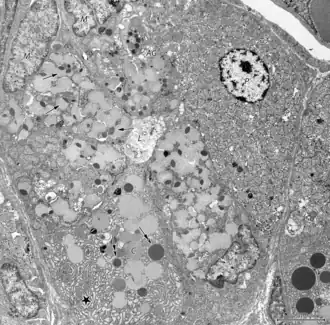

Ultraestructura

Con el microscopio electrónico se han podido describir, ubicar y sistematizar las células que integran las glándulas gástricas.[7][2]

- Células mucosas tapizan la superficie luminal, el sector de la foveola (fosita o gastric pit) y el istmo de la glándula. Segregan el mucus necesario para la protección frente al ácido clorhídrico secretado por sus vecinas. Cuando los gránulos secretores se alinean a lo largo de la membrana apical, la célula anterior a la de la fosa, se convierte en célula fosa. Ambas las células de la foveola, como las células previas a la misma, migran hacia la superficie gástrica donde finalmente se pierden.[8]

- Células parietales u oxínticas son un tipo de célula ubicadas en la parte superior de las glándulas del estómago. Se encuentran mayoritariamente en el cuerpo gástrico y más escasamente en el antro. Son las encargadas de la producción de ácido gástrico y de factor intrínseco.

- Células principales (Chief cells) (también llamadas zimogénicas o peptídicas) son las encargada de la secreción de pepsinógeno, lipasa gástrica y quimosina.

- Células G son un tipo de células entero-endócrinas situadas en el glándula encargadas de producir gastrina.

- Células ECL similares a las enterocromafines, son un tipo de células neuroendocrina encontrada en estrecha cercanía de las células parietales. Estas células se encuentran en las regiones del fundus y cuerpo, sintetizan, almacenan y segregan histamina.